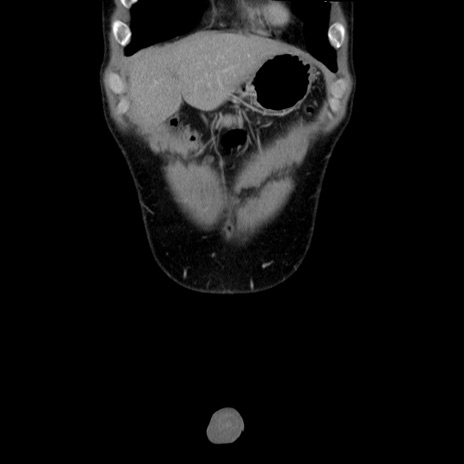

症例36(冠状断像)

【症例】20歳代 男性

【主訴】心窩部痛

【現病歴】今朝より上腹部痛あり。一旦軽快していたが再度出現したため救急要請。昨日夕に白身の魚を含む刺身を食べた。

【身体所見】BP 136/89mmHg、HR 74/min、BT 37.0℃、腹部:膨満、軟、心窩部に圧痛あり。反跳痛なし、筋性防御なし、腸雑音やや亢進あり。

【データ】WBC 17700、CRP 0.48